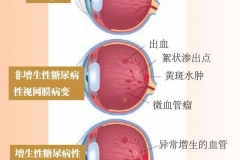

健康科普:糖尿病患者、孕婦、胖子怎么吃健康?試試這個門診

健康科普:糖尿病患者、孕婦、胖子怎么吃健康?試試這個門診

科普中國-樂享健康